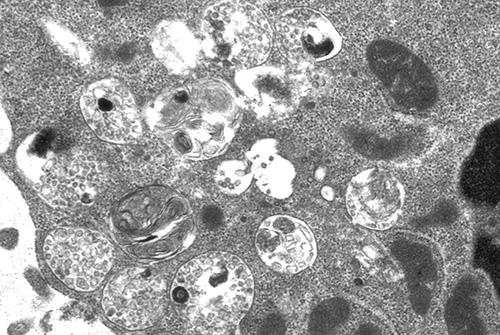

Immune cells slice up antigens in organelles called lysosomes and attach the fragments to complexes that display them on the cell surface in order for these peptides to bind and activate other immune cells. To ensure that they can cut up the antigens, cells steer newly made enzymes to lysosomes by tagging them with M6P molecules. In the rare disease mucolipidosis II, patients can't synthesize M6P, and their lysosomes fill up with undigested molecular junk known as storage material.

To find out how loss of M6P affects different kinds of immune cells, researchers in Germany used mutant mice that mimic symptoms of mucolipidosis II patients. The animals' B cells were abnormal. Their lysosomes bulged with storage material, and they were poor at dismembering antigens and breaking down a protein that prevents the presentation of antigen fragments. The researchers also found that key processes related to maturation, proliferation, and differentiation were impaired in B cells from the mutant mice, and the cells were defective and produced fewer antibodies than normal. Importantly, they confirmed that B cells from patients with the disease present similar defects in antibody synthesis.